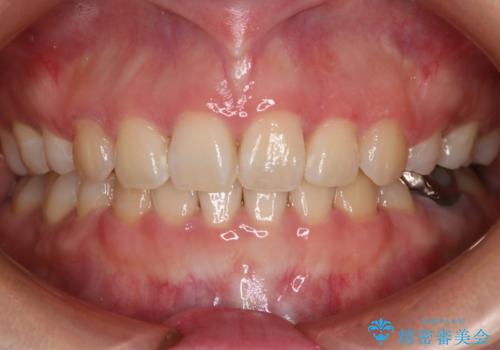

【モニター】八重歯と正中を改善 ワイヤー装置の抜歯矯正

担当医 藤巻太一朗